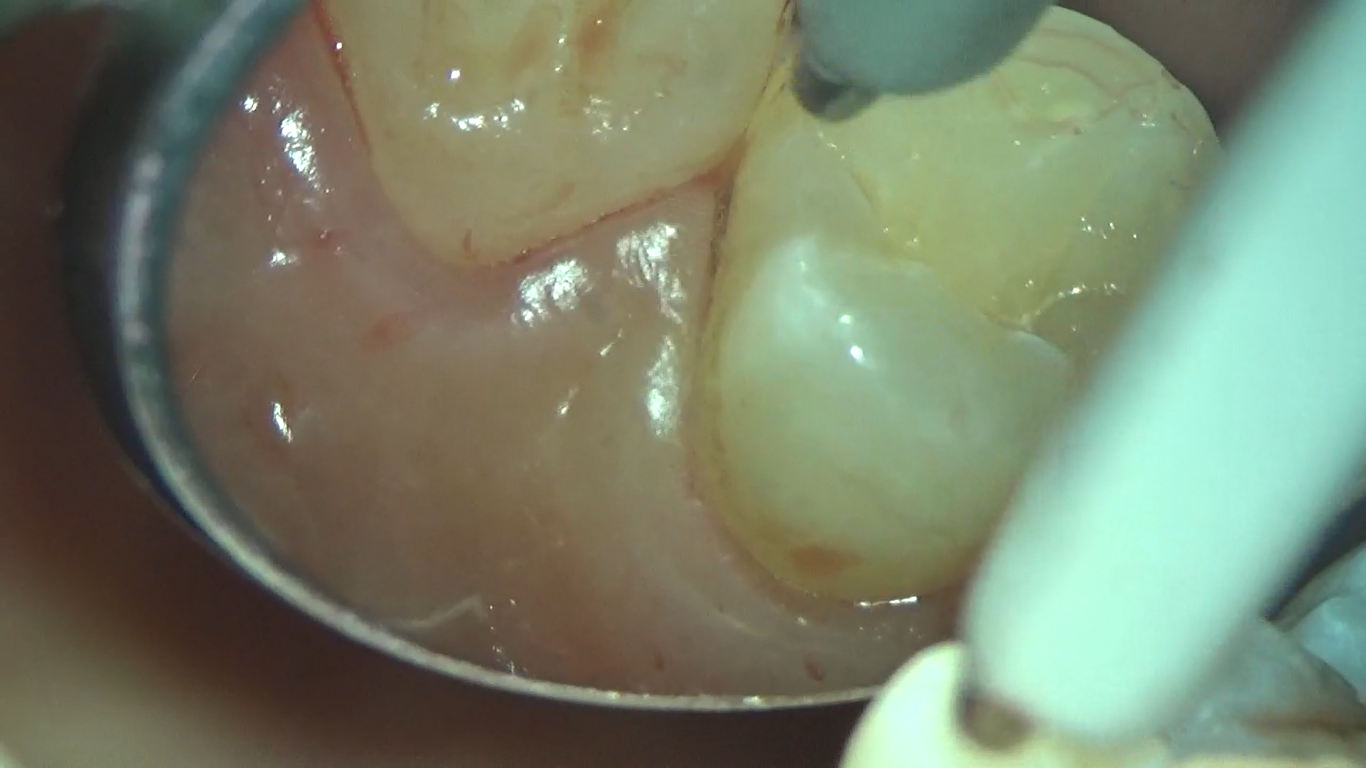

マイクロスコープを使用した歯周治療

こんにちは。 南館歯科クリニック、歯科衛生士の佐藤です。 今回は、マイクロスコープを使用した「歯周治療」の一部をご紹介します。 20代 男性 初期~中度の歯周病 歯周病の治…